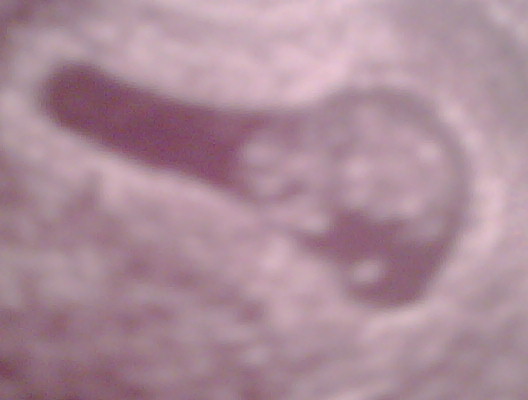

ok well maybe not....but exciting for me!!!! first images of the new kiddo!!!!